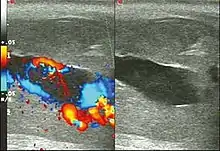

Blood gas testing the blood from the cavernosa of the penis can help in the diagnosis.[3] If the low-flow type of priapism is present, the blood typically has a low pH, while if the high-flow type is present, the pH is typically normal.[3] Color Doppler ultrasound may also help differentiate the two.[3] Testing a person to make sure they do not have a hemoglobinopathy may also be reasonable.[3]

Ultrasonography

Penile ultrasonography with Doppler is the imaging method of choice, because it is noninvasive, widely available, and highly sensitive. By means of this method, it is possible to diagnose priapism and differentiate between its low- and high-flow forms.[11]

In low-flow (ischemic) priapism the flow in the cavernous arteries is reduced or absent. As the condition progresses, there is an increase in echogenicity of the corpora cavernosa, attributed to tissue edema. Eventually, changes in the echotexture of the corpora cavernosa can be observed due to the fibrotic transformation generated by tissue anoxia.[11]

In high-flow priapism normal or increased, turbulent blood flow in the cavernous arteries is seen. The area surrounding the fistula presents a hypoechoic, irregular lesion in the cavernous tissue.[11]